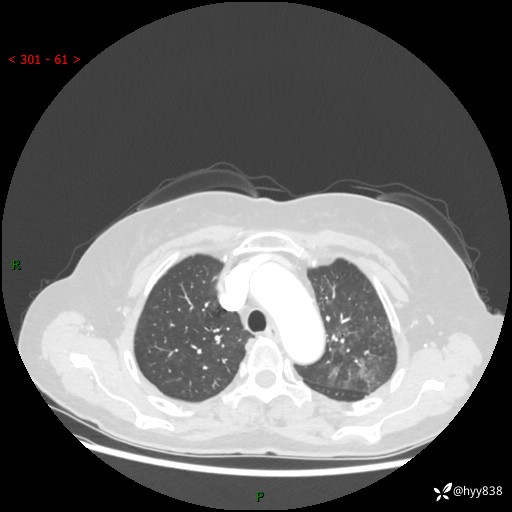

老年女性,偶然发现肺结节10天。结节不大,空洞不小,还牵拉胸膜---结果公布~

胸部CT增强(2024.8.2)